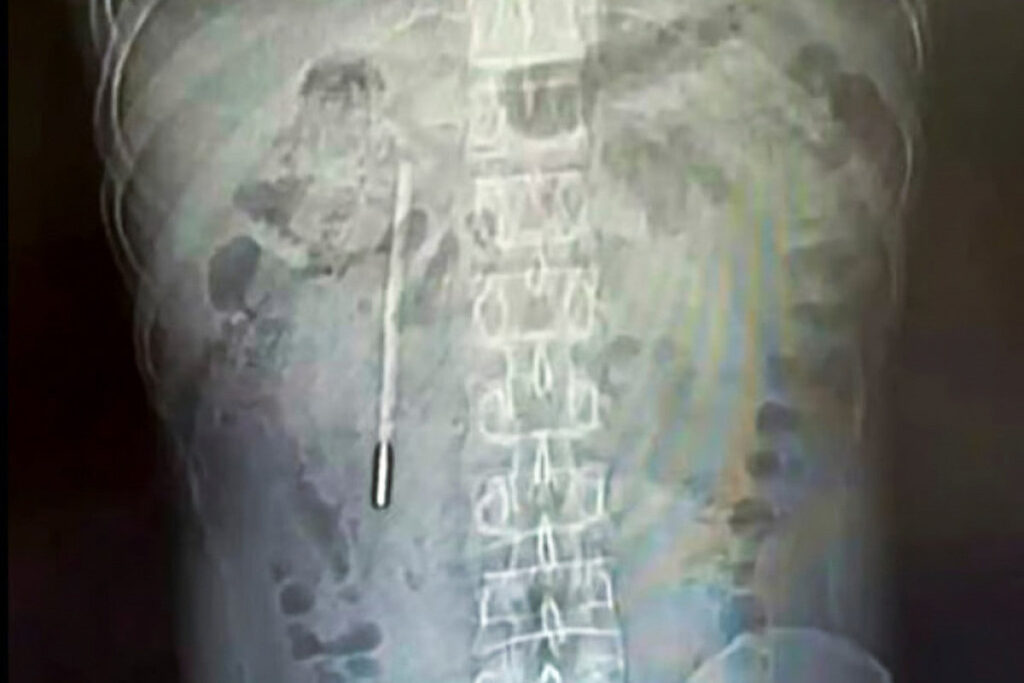

Xitoyda erkak 20 yil davomida ichakda termometr bilan yashagan

Xitoyda 32 yoshli erkak 20 yil avval tasodifan yutib yuborgan simobli termometr uning ichak qismida qolib ketgani aniqlanib, shifokorlar tomonidan olib tashlandi. Bu haqda South China Morning Post nashri xabar berdi.

Unga ko‘ra, erkak qorin og‘rig‘i shikoyati bilan shifoxonaga murojaat qilgan. Tekshiruvlar davomida uning o‘n ikki barmoqli ichagida begona jism borligi aniqlangan. Keyinchalik ma’lum bo‘lishicha, u ushbu termometrni o‘smirlik davrida tasodifan yutib yuborgan, biroq qo‘rquv sababli bu haqda ota-onasiga aytmagan va vaqt o‘tishi bilan voqeani unutib yuborgan.